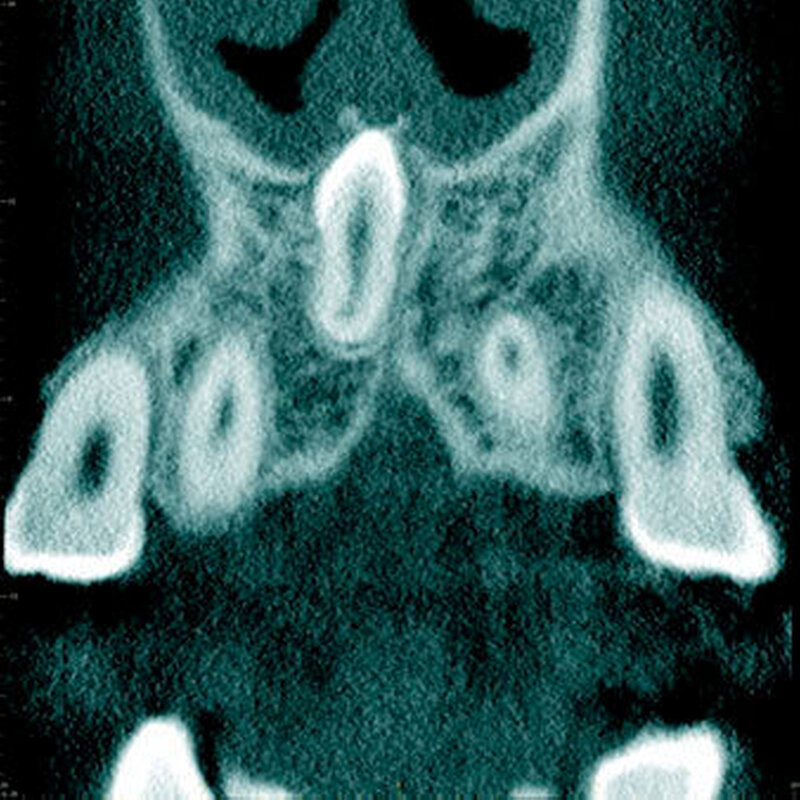

Radiologisch erscheint der Zahnfollikel um retinierte überzählige Zähne als eine dünne perikoronale Radio-luzenz, welche in der Regel nicht breiter als 3 mm ist [Mossaz et al., 2014] (Abbildung 19). Andere Autoren betrachten eine Breite von 2 mm als physiologisch [Tyrilogou et al., 2005]. Bis heute fehlen aber klare Angaben zu den normalen Dimensionen des Zahnfollikels, das heißt, es ist radiologisch nicht eindeutig zu erkennen, wann ein zystischer Prozess vorliegt [Villalba et al., 2012]. Studien berichteten über eine (pathologische) Erweiterung des Follikularraums in 1,4 Prozent bis 5,3 Prozent der überzähligen Zähne [von Arx 1990; Tyrologou et al., 2005; Liu et al., 2007; Hyun et al., 2009; Mossaz et al., 2014]. Dagegen sahen Koch und Mitarbeiter (1986) bei 54 überzähligen Zähnen keine Erweiterung des perikoronaren Raumes während des Beobachtungsintervalls (Mittelwert: 7,3 Jahre).